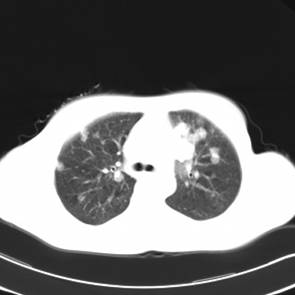

影像学检查:

CT左侧乳腺癌保乳治疗术后,双肺发转移瘤;

两个月后患者到医院复查CT发现,双肺发转移瘤明显实现了瘤体萎缩。